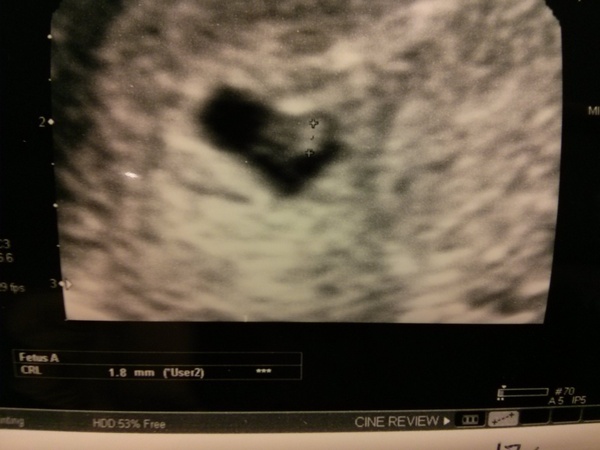

Thank you all so much for your good luck vibes. I think we are ok! I told the obstetrician I was 6+6 going from LMP but I didn't think I'd ov'ed until CD18. She did an abdominal scan but was having trouble seeing anything so got in the super experienced sonographer who did an internal dildocam and found the yolk sac straight away and a teeny tiny 1.8mm fetal pole. They said that it all looked good and matched with the dates I thought. They said they wouldn't expect to see a heartbeat until it is at least 7mm (and it should now grow about 1mm everyday), but possibly not even then so they have booked me in for another scan 2 weeks today when I should be about 8 weeks. They said the brown spotting is probably harmless and as far as they could see at this stage everything looked ok, but obviously couldn't give me any guarantees. So please all keep sending your positive thoughts!